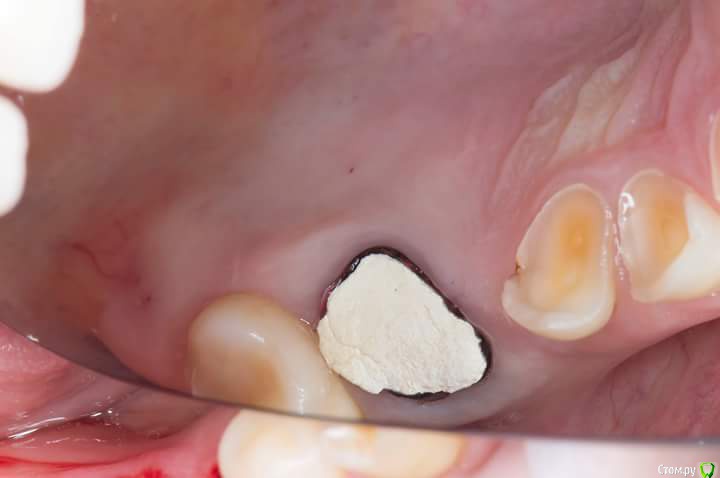

Sampson Опубликовано 3 июля, 2018 Поделиться Опубликовано 3 июля, 2018 1. Забор трансплантата из области 16-17Ушивание2.пластика предверия штрипсой по Урбану3. Установка 2 импланта Adin rpУшивание4.удаление 16. Prf в лунку,поверх губка Альванес. 7 Ссылка на комментарий

Sampson Опубликовано 13 июля, 2018 Автор Поделиться Опубликовано 13 июля, 2018 Вид через 7 дней.Не болит, нет отека.Швы на 45 46 тугие.при подтягивании безболененые и кровоточат. Ссылка на комментарий

Sampson Опубликовано 7 августа, 2018 Автор Поделиться Опубликовано 7 августа, 2018 месяц спустя Ссылка на комментарий